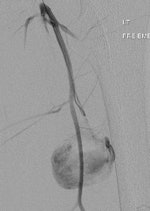

Plain radiography and CT are the most commonly used modalities for imaging of gunshot wounds, but angiography and MRI are playing an increasing role, according to research presented at the 2011 U.K. Radiological Congress (UKRC) in Manchester.

Doctors involved in the care of these patients need to understand the patterns and mechanisms of the injuries, he explained. To accurately interpret images of gunshot wounds, a basic knowledge of ballistics is important, especially the factors affecting the extent and type of tissue damage. Such knowledge is useful not only for evaluating acute injuries but also for determining the path of the missile, awareness of missile fragmentation, and embolization, thus contributing to the overall clinical, and often the forensic, picture.

The two mechanisms of tissue injury that account for the majority of damage caused by a bullet are direct crushing of tissue by the projectile (causing a permanent cavity) and temporary cavitation, which stretches and tears surrounding tissues. Increased velocity, fragmentation, deformation, and rolling/spinning of the bullet will cause more damage by both these mechanisms, he pointed out.